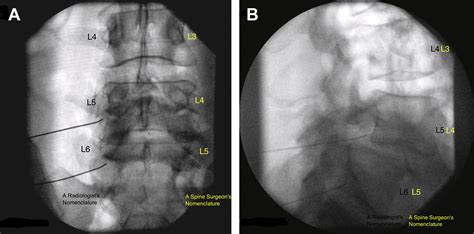

• Imaging Studies: Imaging techniques such as X-rays, MRI, and CT scans are crucial for visualizing the anatomy of the lumbosacral region. These studies can reveal degenerative changes, herniated discs, spinal stenosis, and other abnormalities.